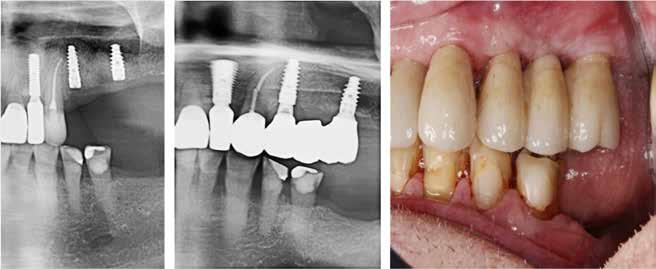

Klik ind på Tandlægebladet.dk og opret en reklamation, så sørger vi for, at bladet lander i din postkasse.

Klik ind på Tandlægebladet.dk og vælg om os

BAGGRUND – Transverselle okklusionsafvigelser kombineret med en vækstbetinget kæbedeformitet korrigeres sædvanligvis ved en sektioneret Le Fort 1-osteotomi eller kirurgisk assisteret ganeekspansion. Ved ekstreme transverselle skeletale diskrepanser mellem maksillen og mandiblen kan der være indikation for transversel udvidelse af mandiblen ved hjælp af mandibulær midtlinjeosteotomi eller mandibulær midtlinjedistraktionsosteogenese.

PATIENTTILFÆLDE – En 15-årig dreng med infantil autisme blev henvist fra Hjørring Kommunes Tandpleje til Kæbekirurgisk Afdeling, Aalborg Universitetshospital, for ortodontisk-kirurgisk behandling af et stort horisontalt maksillært overbid uden kontakt på nogen af tænderne. Den vækstbetingede kæbedeformitet blev korrigeret ved hjælp af ortodonti og mandibulær midtlinjedistraktionsosteogenese efterfulgt af en sektioneret Le Fort I-osteotomi og bilateral sagittal splitosteotomi.

KONKLUSION – Mandibulær midtlinjedistraktionsosteogenese er en forudsigelig behandlingsmodalitet til transversel udvidelse af mandiblen. Imidlertid er behandlingen forbundet med en betydelig risiko for recidiv samt biologiske og tekniske komplikationer, hvorfor mandibulær midtlinjedistraktionsosteogenese udelukkende anbefales til korrektion af ekstreme vækstbetingede transverselle okklusionsafvigelser.

EMNEORD Jaw abnormalities | malocclusion | orthodontics | orthognathic surgery

PERNILLE SAGBAKKEN, tandlæge, Odontologisk Institut, Det Sundhedsvidenskabelige Fakultet, Københavns Universitet

ANNETTE DALGAARD KJELLERUP, specialtandlæge i ortodonti, Kæbekirurgisk Afdeling, Aalborg Universitetshospital